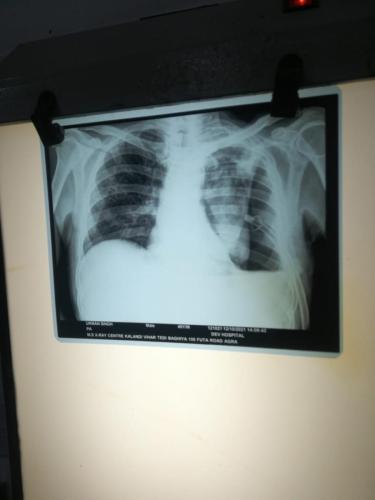

Photo Gallery Dr. Monika Gupta - Photo Gallery 7 5 2 8 6 Dr. Atul Kumar Gupta - Photo Gallery « ‹ of 3 › » Video Gallery